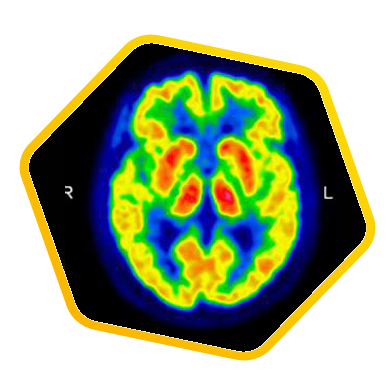

Positron Emission Tomography/Computed Tomography (PET/CT) is one of the most effective methods for cancer imaging and diagnosis. During the course of cancer development, metabolic changes always come earlier than structural or morphological changes in tissues and organs. Therefore PET/CT being a powerful camera capable of imaging our metabolic functions, it can facilitate early cancer detection and staging through the identification of the tumor biological characteristic.

PET tracers work as the biological imaging probe. Some of the commonly applied PET tracers include: PET radionuclide labelled deoxyglucose, acetate, DOTA-conjugated peptides, prostatic specific membrane antigen, etc. After injection, the tracer is absorbed based on organs’ structure as well as cell metabolism. The patient is then scanned with the PET/CT scanner to pick up any signals emitted from the tracer and hence the lesion location can be identified and uptake can be quantified. With this unique piece of medical information, we can locate lesions precisely and also help the assessment of treatment effectiveness.

PET/CT offers multiple parameters to quantify the cell activity which has a broad clinical application like cancer, cardiac, neurological diseases, etc. Apart from the most common “Standardized Uptake Value (SUV)”, the latest application involves mathematic calculation on the image data to retrieve even more unique dynamic parameters (such as “Patlak Analysis” for absolute metabolic rate, distribution volume of the pharmacology, theranostics and dose planning in radiotherapy). It creates unlimited possibilities in diagnosis and treatment planning.